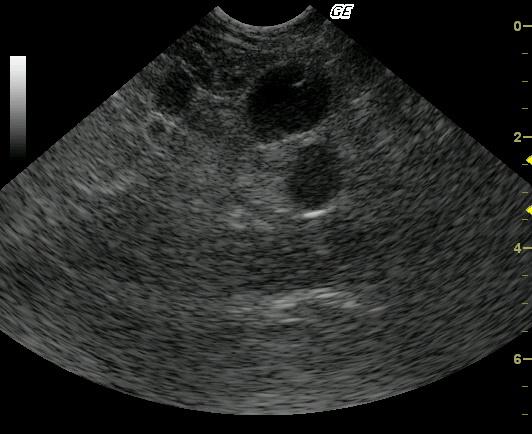

This 2-year-old Maine Coon cat was presented after five days of vomiting and anorexia. The physical examination revealed mildly thickened intestines and 5% dehydration. Blood analysis revealed mild regenerative anemia and slightly elevated globulin levels.